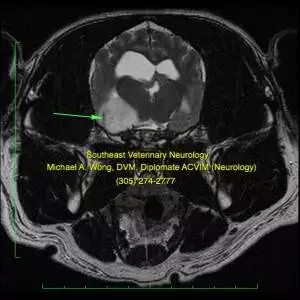

MRI of the brain of a cat showing a meningioma.

Mri Dog Brain Glioma

MRI of the brain of a dog showing a glioma.